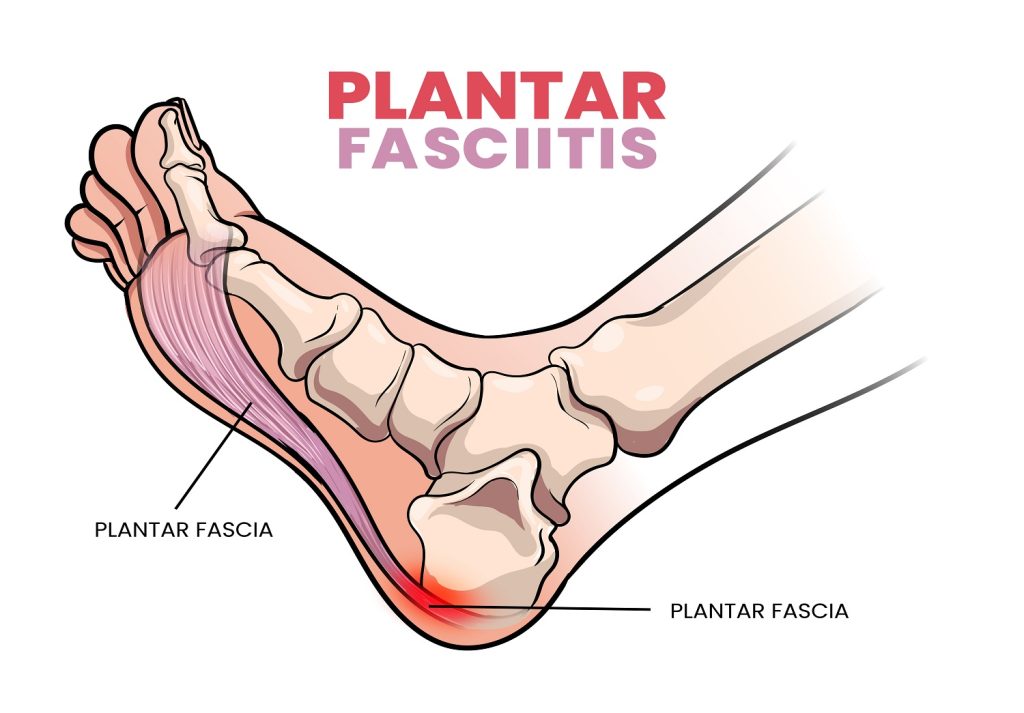

What is Plantar Fasciitis?

Your plantar fascia is a thick band of connective tissue that runs along the bottom of your foot, connecting your heel bone to your toes. Its job is to support your foot arch and absorb shock during walking and running. Plantar fasciitis occurs when this tissue becomes overloaded, irritated, or inflamed — typically due to overuse or poor foot mechanics. Contrary to its name, it’s not always a true “inflammatory” condition, but more often a degenerative or overload-related injury.